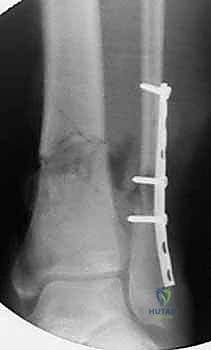

يبدأ التشخيص بالفحص السريري الدقيق لتقييم حالة الجلد، النبض، والأعصاب. يتبع ذلك إجراء الأشعة السينية (X-rays) من زوايا متعددة لتحديد موقع وشكل الكسر بدقة. في حالات الكسور المعقدة أو التي تمتد إلى مفصل الركبة أو الكاحل، يطلب البروفيسور هطيف إجراء أشعة مقطعية (CT Scan) للحصول على صورة ثلاثية الأبعاد تساعد في التخطيط الجراحي الدقيق.

الخيارات العلاجية: مقارنة شاملة بين الطرق التقليدية والحديثة

لا يوجد علاج واحد يناسب جميع حالات كسور الساق. يعتمد اختيار العلاج على نوع الكسر، مكانه، حالة الأنسجة الرخوة، والعمر والحالة الصحية للمريض. إلا أن التوجه العالمي الحديث، والذي يطبقه أ.د. محمد هطيف بصرامة، يميل بقوة نحو التدخل الجراحي بالتسمير النخاعي لضمان أفضل النتائج الميكانيكية.

| دواعي الاستعمال | كسور بسيطة غير متحركة، الأطفال | كسور قريبة جداً من المفصل (الركبة/الكاحل) | الكسور المفتوحة بشدة، التلوث العالي | أغلب كسور الساق (الوسطى والسفلية) |

| الاستقرار الميكانيكي | ضعيف إلى متوسط | جيد | جيد | ممتاز (يتحمل الوزن مبكراً) |

| حجم الجرح (الندبة) | لا يوجد | جرح طولي كبير | ثقوب متعددة للأسياخ | جروح صغيرة جداً (تدخل محدود) |

| سرعة التعافي والمشي | بطيئة جداً (أشهر) | متوسطة | بطيئة | سريعة جداً (أسابيع قليلة) |

| خطر العدوى | منخفض | متوسط إلى عالي | عالي (حول أسياخ التثبيت) | منخفض جداً |

| الحفاظ على التروية الدموية | نعم | يتطلب تجريد العظم من السمحاق (يؤثر على التروية) | نعم | ممتاز (لا يتم المساس بغلاف العظم) |